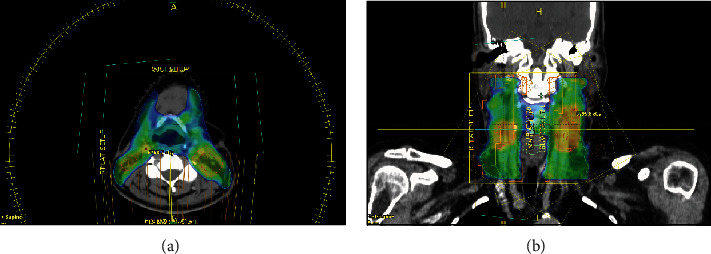

Neuroendocrine neoplasms (NENs) are rare in the head and neck region, with the larynx being the most common site. To date, nearly 700 cases of laryngeal neuroendocrine carcinoma (NEC) have been reported in the literature, with an estimated incidence as low as 0.23%. This type of cancer is more prevalent among men aged 50-83 who are heavy smokers. NENs encompass paragangliomas and epithelial neoplasms. The latter categories include neuroendocrine tumors, or typical carcinoids, and NECs, or atypical carcinoids. Due to their nonspecific and often misleading presentation, and given the rarity of this condition, optimal management lacks standardization. Treatment typically involves a combination of surgery, chemotherapy, and radiotherapy. We present a case of supraglottic laryngeal NEC in a 61-year-old female nonsmoker. The patient underwent endoscopic excision followed by adjuvant radiotherapy.